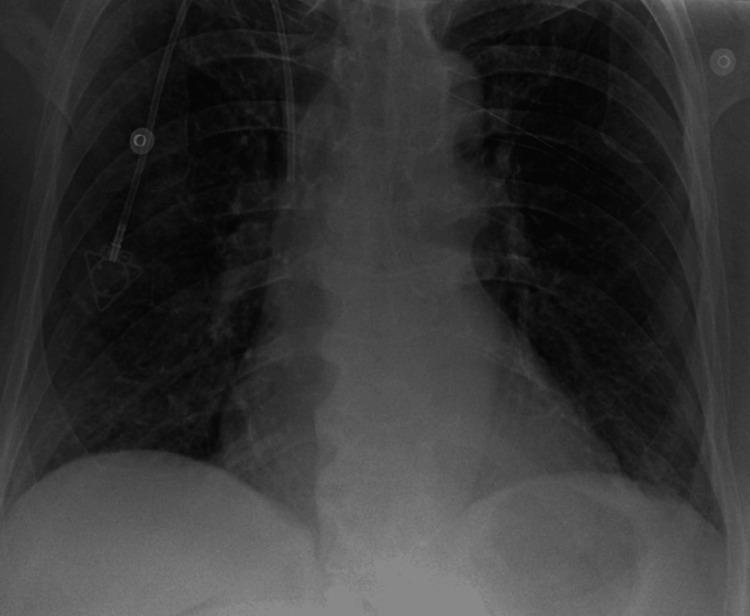

Imatinib, a tyrosine kinase inhibitor, is widely used for treating gastrointestinal stromal tumors (GISTs) and chronic myeloid leukemia (CML). While commonly associated with mild fluid retention, significant pleural effusion is an uncommon but potentially serious adverse effect. We present a case of recurrent pleural effusions secondary to imatinib therapy in a 62-year-old female patient with metastatic lung adenocarcinoma and a concurrent GIST harboring an exon 9 mutation. She was initiated on imatinib 400 mg daily, later increased to twice daily. Within weeks, she developed progressive dyspnea, and imaging revealed large bilateral pleural effusions. Pleural fluid analysis demonstrated an exudative effusion, with cytology and microbiological studies ruling out infection or malignancy. Cardiac function was preserved, and there were no signs of volume overload. She underwent multiple thoracenteses for symptomatic relief. Due to recurrent pleural effusions, imatinib was permanently discontinued, leading to complete resolution of the effusions. Subsequent treatment with sunitinib was not tolerated due to severe mucositis and cytopenias. Despite discontinuation of targeted therapy, both her GIST and metastatic lung cancer remained stable under surveillance. While pleural effusions are frequently reported with dasatinib, they are rare with imatinib. The proposed mechanisms include inhibition of platelet-derived growth factor receptors (PDGFRs), leading to increased vascular permeability, impaired lymphatic drainage, and renal sodium retention. Dose reduction may mitigate fluid retention; however, our patient developed significant pleural effusions at standard dosing, necessitating treatment discontinuation. This case underscores the importance of recognizing pleural effusion as a rare but serious adverse effect of imatinib therapy. Clinicians should maintain a high index of suspicion for drug-induced pleural effusions, particularly in the absence of other etiologies, and consider discontinuation if clinically indicated. Early recognition and management can prevent complications and improve patient outcomes.

伊马替尼是一种酪氨酸激酶抑制剂,广泛用于治疗胃肠道间质瘤(GIST)和慢性粒细胞白血病(CML)。虽然通常与轻度液体潴留有关,但大量胸腔积液是一种罕见但可能严重的不良反应。我们报告一例62岁女性患者,患有转移性肺腺癌和同时存在外显子9突变的GIST,因伊马替尼治疗继发反复胸腔积液。她开始每天服用400毫克伊马替尼,后来增加到每天两次。几周内,她出现进行性呼吸困难,影像学检查显示双侧大量胸腔积液。胸腔积液分析显示为渗出性积液,细胞学和微生物学研究排除了感染或恶性肿瘤。心脏功能保持正常,没有容量超负荷的迹象。她接受了多次胸腔穿刺以缓解症状。由于反复出现胸腔积液,伊马替尼被永久停用,积液完全消退。随后使用舒尼替尼治疗因严重粘膜炎和血细胞减少而无法耐受。尽管停用了靶向治疗,但在监测下她的GIST和转移性肺癌均保持稳定。虽然达沙替尼经常报告有胸腔积液,但伊马替尼引起的则很少见。推测的机制包括抑制血小板衍生生长因子受体(PDGFR),导致血管通透性增加、淋巴引流受损和肾钠潴留。减少剂量可能减轻液体潴留;然而,我们的患者在标准剂量下出现了大量胸腔积液,需要停药。该病例强调了认识到胸腔积液是伊马替尼治疗罕见但严重的不良反应的重要性。临床医生应高度怀疑药物性胸腔积液,特别是在没有其他病因的情况下,并在临床指征明确时考虑停药。早期识别和管理可以预防并发症并改善患者预后。